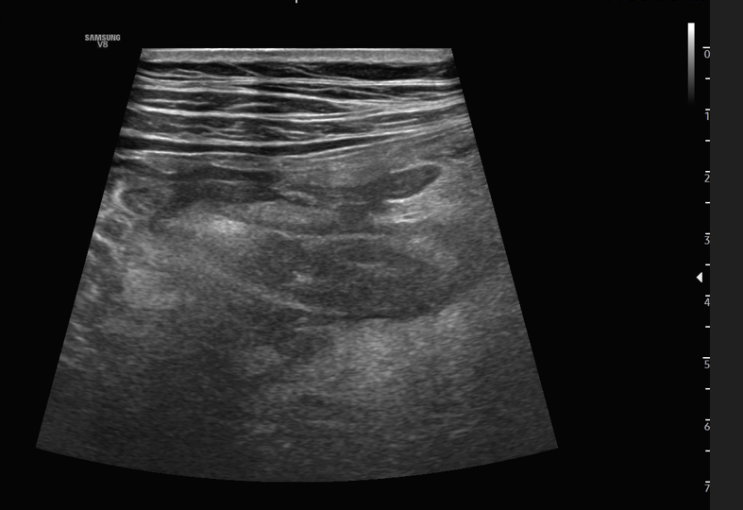

[금호동 신장초음파] 서울으뜸내과, 우연히 발견된 신장암

#왕십리내과 #금호동내과 #상왕십리내과 #뚝섬역내과 #성동구내과 #성수동내과 안녕하세요? 서울으뜸내과입...